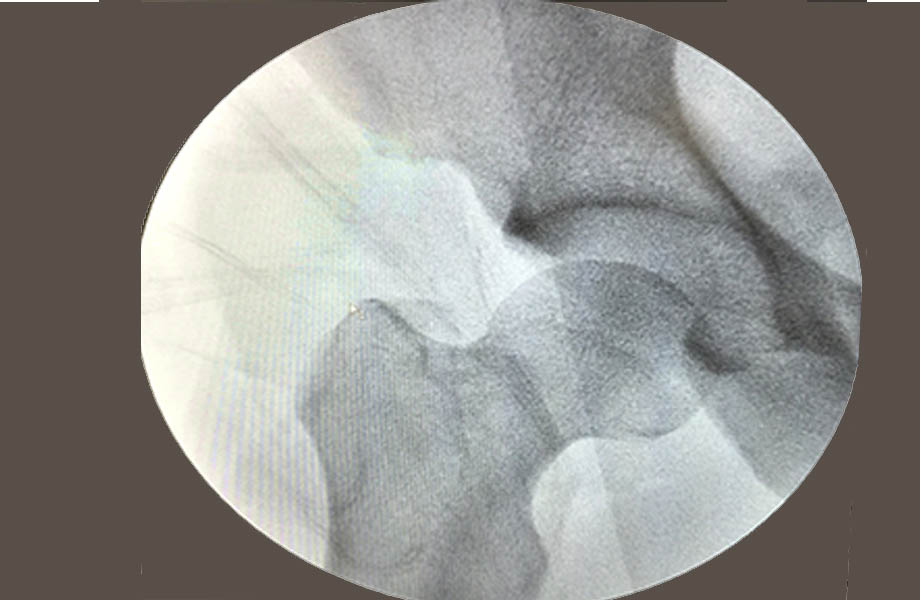

Most often, you will be positioned with your leg pulled in traction. This creates space in the hip joint and allows instruments to access the joint without injuring surrounding cartilage. Accessing the narrow space in the hip joint is complicated by the orientation of surrounding nerves and blood vessels. To ensure the arthroscope and instruments are inserted properly, a portable X-ray device called a fluoroscope will be positioned for use during the procedure.